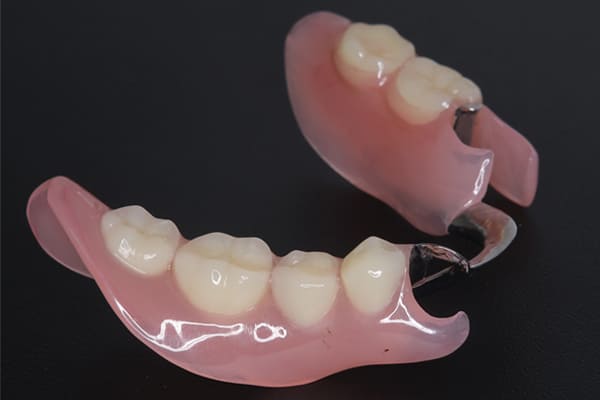

いわいるノンクラスプデンチャーと言われる、入れ歯に金属のバネを用いない入れ歯でしたが、バネに該当する部分が合っていない状態のため浮き上がりがありました。

ノンクラスプデンチャーはバネに金具を用いないため、審美性は優れていますが、沈み込みを防止するストッパーがつけられていない設計や、入れ歯に求めらる基本設計がなされていない場合もたびたび見受けられお痛みがでる場合も多くあります。

笑うと見える、糸切り歯にバネがかかるため、ノンクラスプデンチャーをご希望されて作製しました。

バネに金属を用いておらず自然な見た目となりました。